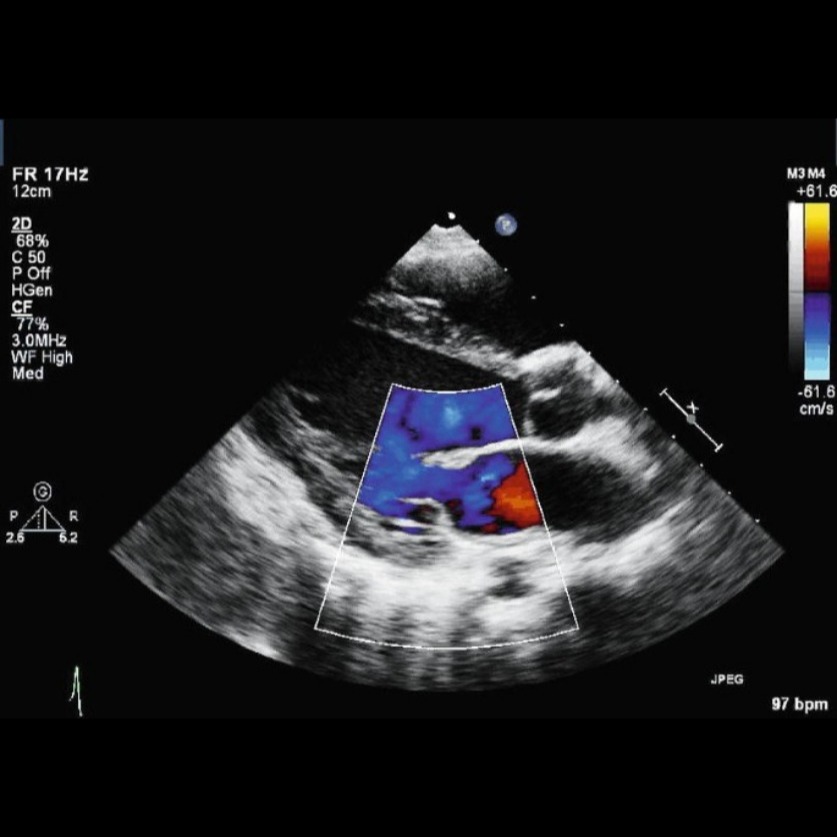

best cardiac clinics near near me Two-dimensional (2D) echocardiography in Rheumatic Heart Disease (RHD) identifies valve damage, most commonly mitral valve issues, with mitral regurgitation in younger people and mitral stenosis in older adults. Key features include thickened, domed anterior mitral valve leaflets, restricted motion, fused commissures, and thickened chordae. Other conditions can include aortic valve disease, a enlarged left atrium, or bicuspid aortic valve in RHD patients.